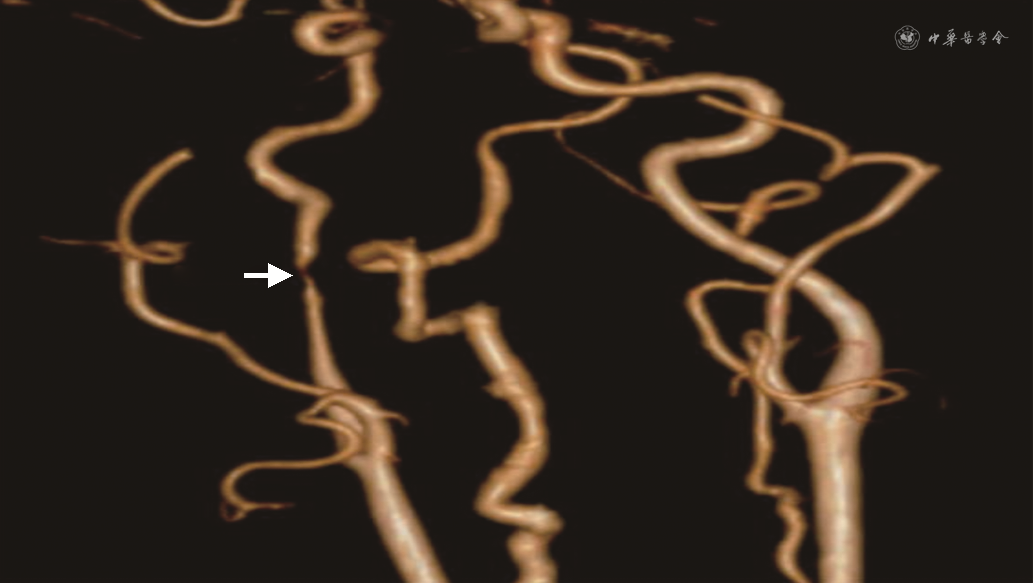

完善24 h动态心电图示:心搏总数77 945次,其中室性心搏4次,室上性心搏53次。心率40~100次,心动过缓心搏26 140次(33.5%),最长RR间期13.37 s,窦性心动过缓伴不齐;夜间显著窦性心动过缓伴不齐;心室长间期>2 s共987次,最长达13.37 s;心率变异性分析:全部窦性心搏RR间期的标准差(SDNN)、RR间期平均值标准差(SDANN)、相邻RR间期差值(rMSSD)升高,PNN 50%正常。室性节律4个,室上性节律51个。心脏彩超示:左室壁运动轻度不协调。颈部CT增强示:右侧咽旁及右侧颈部见多发肿大淋巴结影,部分融合成团,大者位于右颈动脉鞘区,大小4.4 cm×2.0 cm(图1),并包绕推移压迫周围动静脉。颈部CT血管造影(CTA)示:右侧颈内动脉颈段狭窄(图2),考虑肿瘤压迫所致。

本案例中的患者既往无晕厥史,心电图及心脏彩超检查均未提示器质性心脏病。入院后目击患者晕厥发作,表现为无明显诱因突发意识丧失,呼之不应,伴全身大汗,皮肤湿冷,心电监护提示心率及血压下降。考虑患者既往淋巴瘤病史,颈部存在肿大淋巴结,故予进一步完善颈部CT增强及颈部CTA检查,检查结果提示颈动脉窦受压及颈内动脉狭窄。结合患者晕厥发作史及辅助检查,考虑患者晕厥系颈动脉窦综合征(CSS)引起的可能性大。